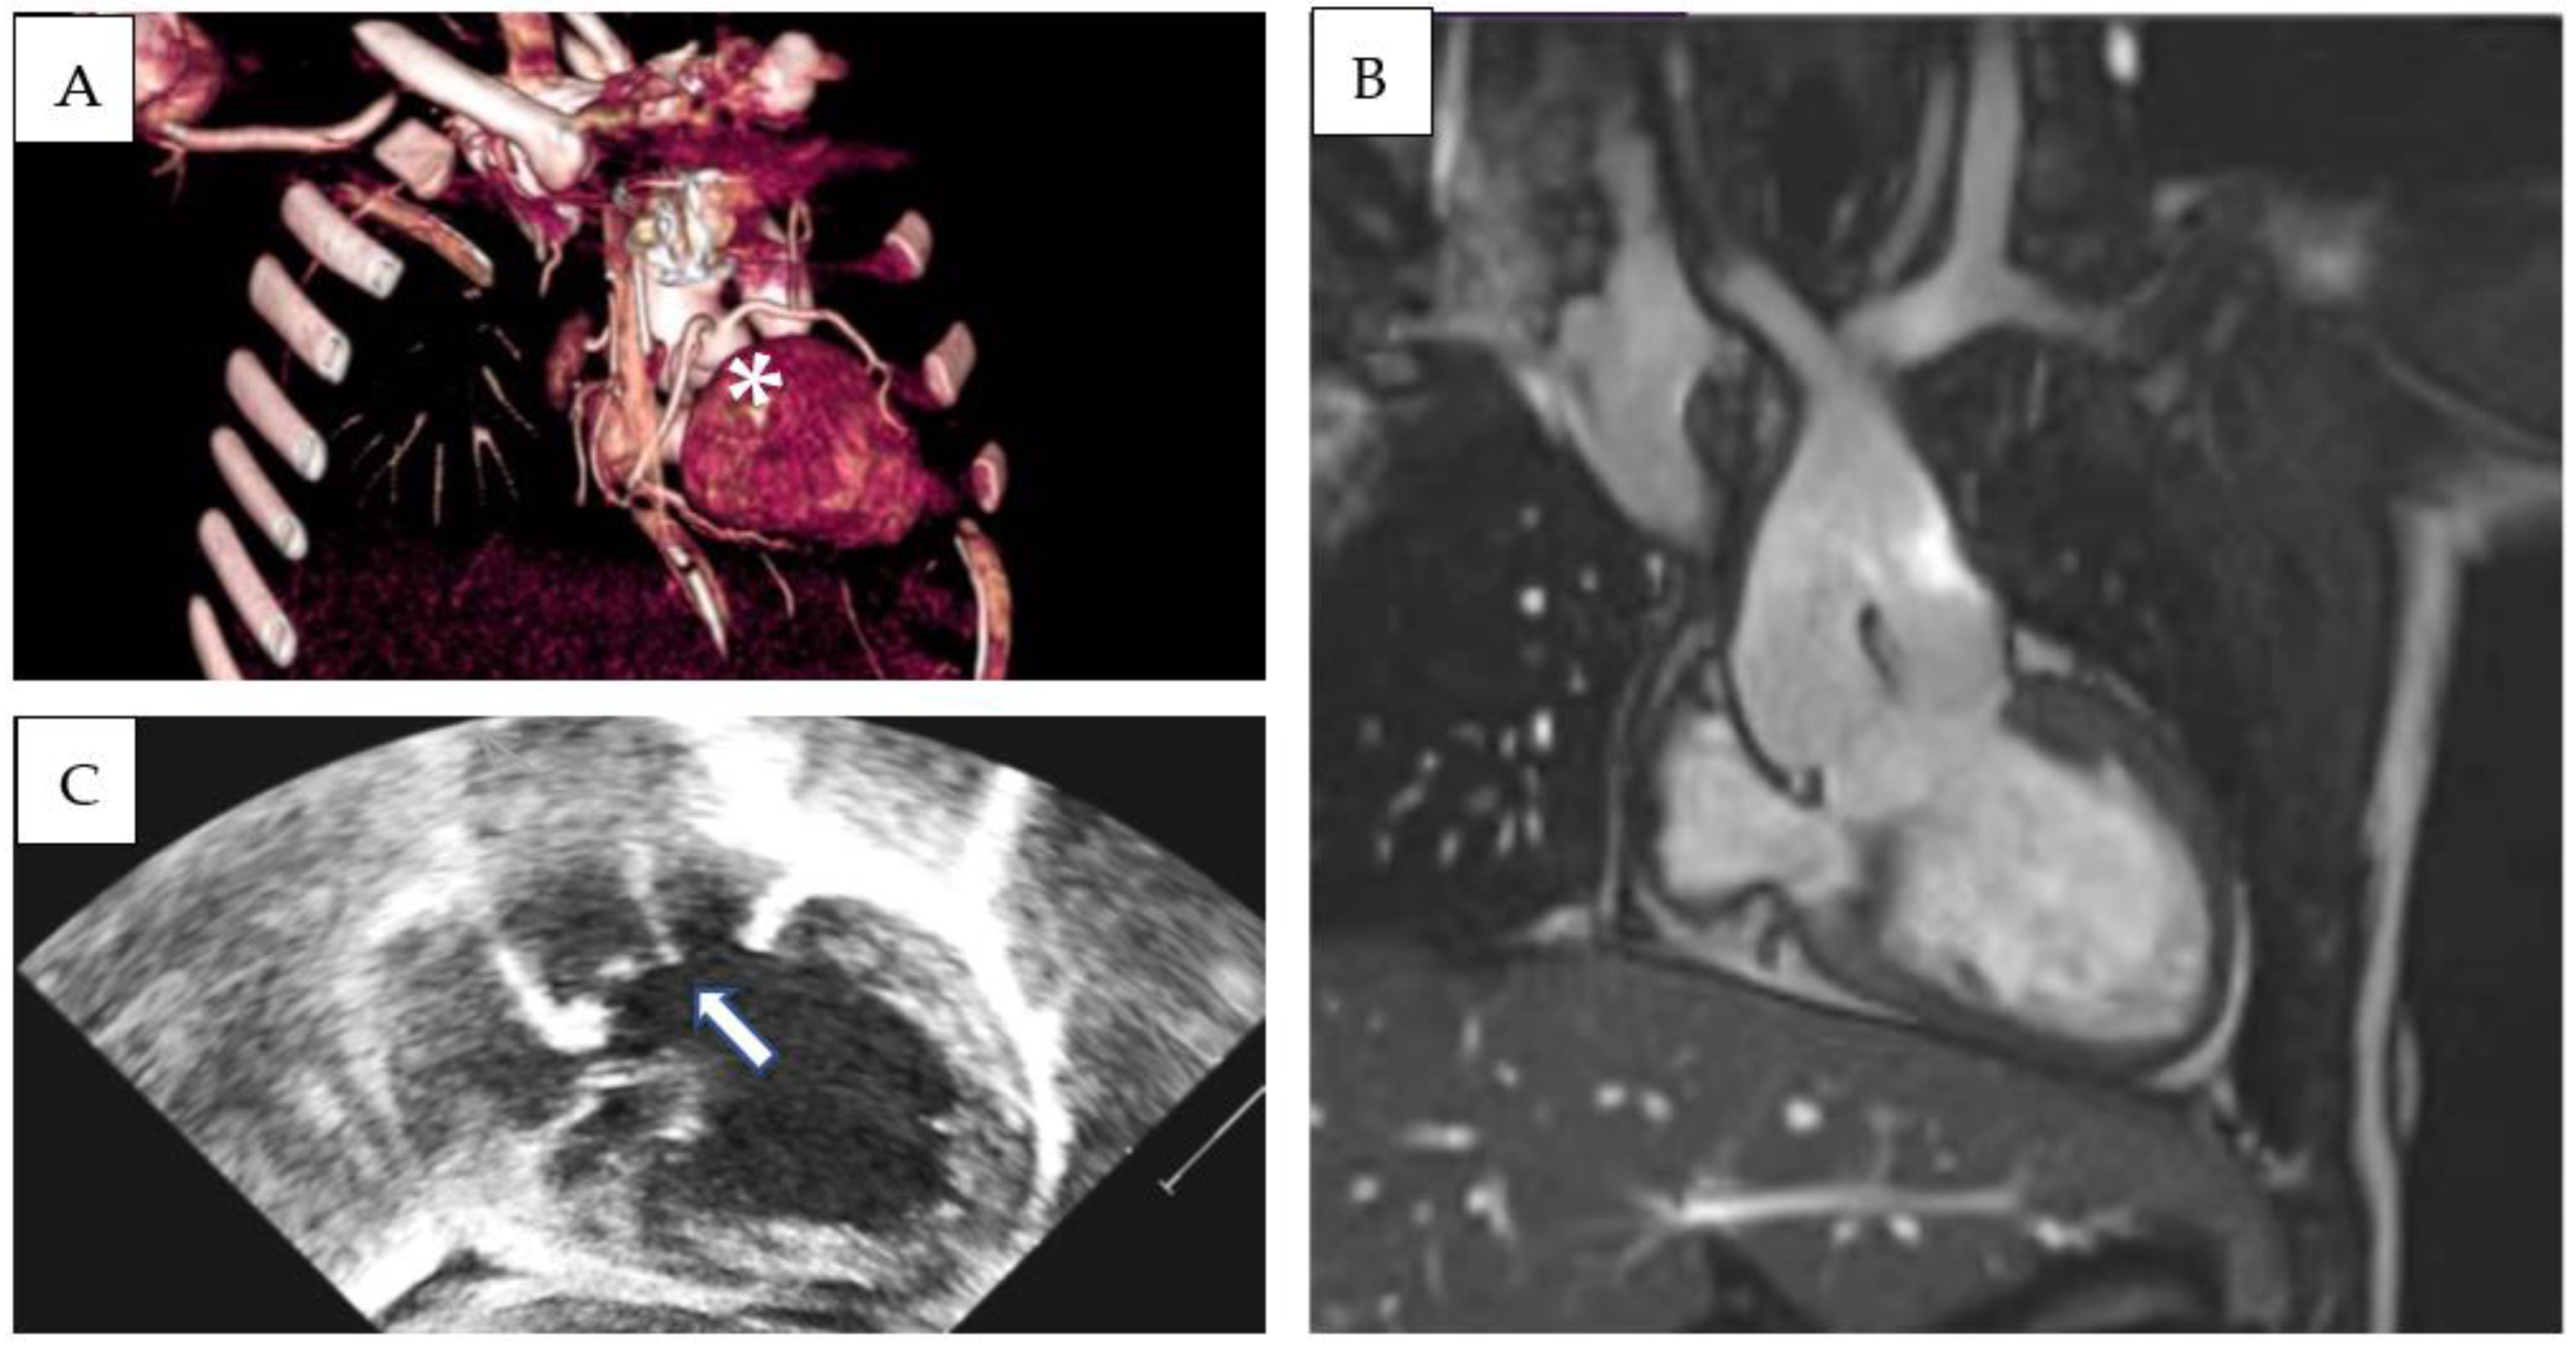

Patient 1 was diagnosed with (S,D,D), double-outlet left ventricle, and a hypoplastic right ventricle. An echocardiographic evaluation revealed situs solitus, D-loop, and severe hypoplasia of the right ventricle. A large, unrestrictive atrial septal defect was present. The aorta overrode a large, doubly committed, juxta-arterial VSD with an absence of infundibular septum. The great arteries were transposed and the aorta was on the right and slightly posterior to the pulmonary artery, which was completely committed to the left ventricle. A tenuous mitro-aortic discontinuity and a well-developed subpulmonary conus were present. Crossed pulmonary arteries were observed, and a subsequent CT scan showed two adjacent, side-by-side coronary ostia, located in the anterior-facing sinus, which gave origin to the left anterior descending (LAD) and the right coronary artery (RCA). The left circumflex artery (LCx) had a retroaortic course originating from the RCA (Figure 1A–C). Pulmonary banding was performed as initial palliation. At 6 months of age, the patient was scheduled for Damus–Kaye–Stansel (DKS), and bidirectional Glenn palliation and extracardiac Fontan palliation were completed at 2.9 years. Follow-up MRI showed mild pulmonary valve regurgitation and pulmonary flow discrepancy between the LPA and RPA (ratio 33% versus 67%), with normal ventricular volumes and preserved ventricular function (LV end-diastolic volume 78 mL/m2, LVEF 53%). To date (follow-up time 5.3 years), the patient is in good clinical condition and his arterial oxygen saturation is stable (SpO2 85%).

Figure 1.

Three-dimensional CT-scan (A), MRI (B), and echocardiographic (C) subcostal view showing double-outlet left ventricle, subaortic VSD, d-transposed aorta and Damus–Kaye–Stansel palliation. Absence of an infundibular septum is a common finding (arrow). LAD and RCA originate from two adjacent, side-by-side coronary ostia from the anterior-facing sinus (asterisk).